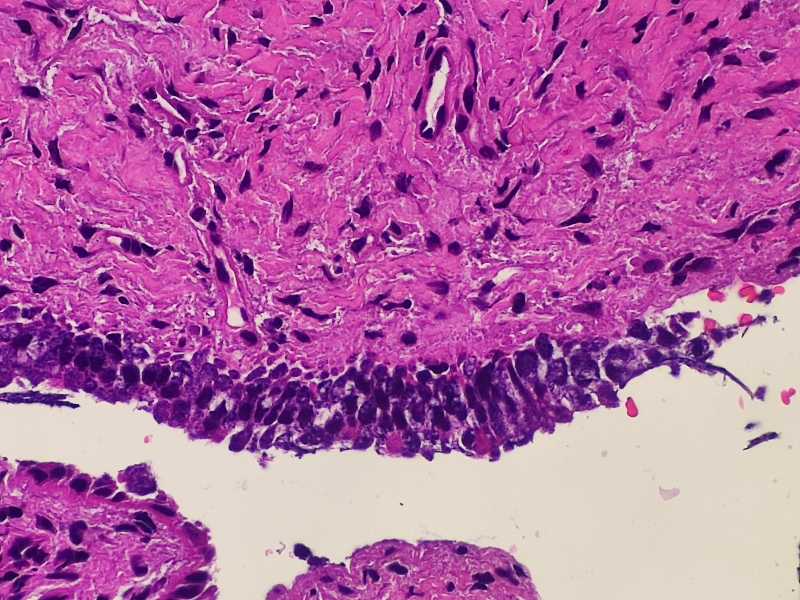

女49岁宫颈糜烂,HPV16和HPV18阳性。宫颈腺体异型原位还是浸润?

腺癌